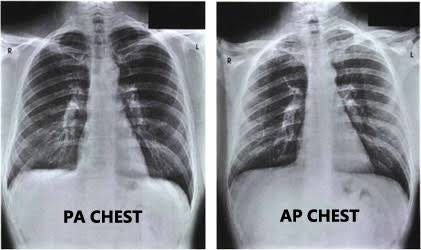

Dica De Radiologia Raio X De Torax Sanar Medicina

www.sanarmed.com